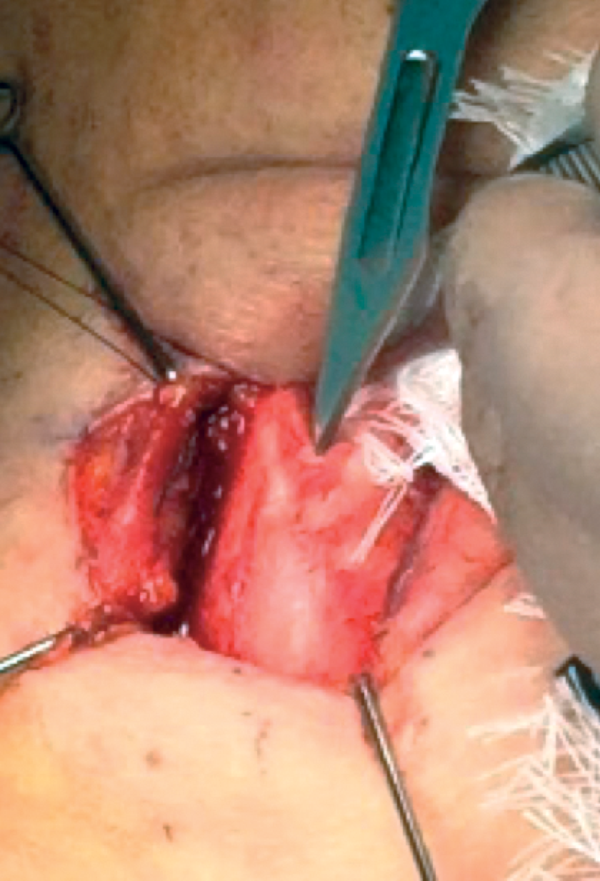

Undermining inner perichondrium

The inner perichondrium is undermined in three stages superiorly and inferiorly (Figure 10).

Stage 1: Using the blunt side of an 11 blade, a 5mm perichondrium incision is made on the superior and inferior outer margins of the thyroid border.

Stage 2: An otology frying pan knife is used to undermine the inner perichondrium in the midline superiorly and inferior by 1mm laterally and in the midline.

Stages 1 and 2 are performed to allow ease of drilling in the midline and later insertion of the titanium bridge. Stage 3 is performed after separation of the thyroid laminae. Take care not to perforate the perichondrium or laryngeal mucosa.

Figure 10: Undermining inner perichondrium.